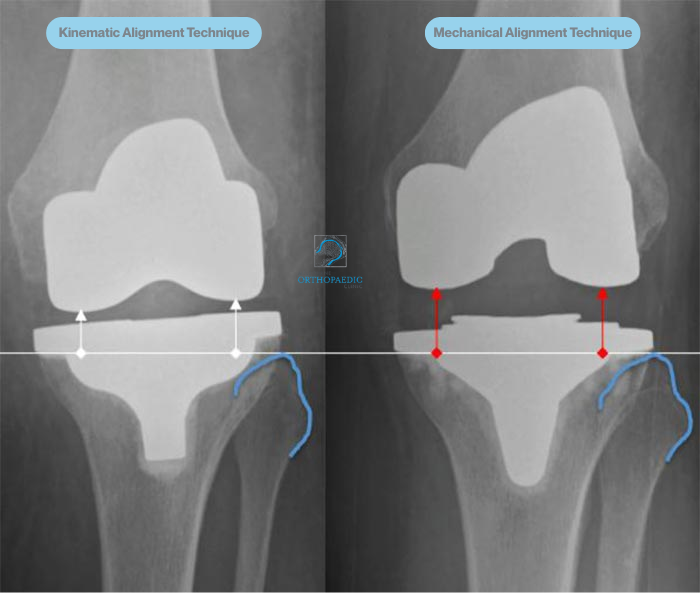

Kinematically aligned (KA), patient-specific total knee replacement is a modern, total knee replacement surgical technique designed to replicate the natural movement of your knee as closely as possible. Unlike traditional methods that follow a standardised mechanical alignment, the KA approach takes into account your individual bone structure, joint angles, and soft tissue balance. With KA, the goal is to position the implants in a way that mirrors how your knee functioned before arthritis developed, enhancing comfort, mobility, and overall satisfaction.

Many patients report that their kinematically aligned total knee replacement feels more “normal” during everyday activities, particularly walking, climbing stairs, or kneeling. Because the joint is aligned to your individual anatomy rather than a generic axis, the surrounding ligaments are more likely to remain in balance, potentially resulting in less stiffness, better range of motion, and a smoother recovery.

Before your surgery, your orthopaedic team will use advanced imaging techniques such as X-rays and a CT scan to create a precise 3D model of your knee. This digital reconstruction allows your surgeon to assess the specific anatomy of your joint in detail, including bone alignment, the degree of wear from arthritis, and any irregularities in joint movement. This model forms the foundation for a fully personalised surgical plan. Every decision, from where bone resections are made to how the implants are aligned is guided by your own anatomy. By tailoring the procedure in this way, the aim is to optimise implant positioning, restore natural joint movement, and enhance the long-term function of your new knee.

Aligning the prosthetic components to match your natural knee

Your knee replacement involves inserting a set of prosthetic components — typically made from a combination of metal alloys and medical-grade plastic — to recreate the surfaces of the joint. These components are positioned to match the natural alignment and movement of your original knee, as closely as possible. In many cases, Prof. Hunt or Prof. Sallen may use computer-assisted techniques or patient-specific guides to help with positioning the implants with a high degree of precision. This helps restore natural joint kinematics and may contribute to improved function, better joint stability, and reduced wear over time.